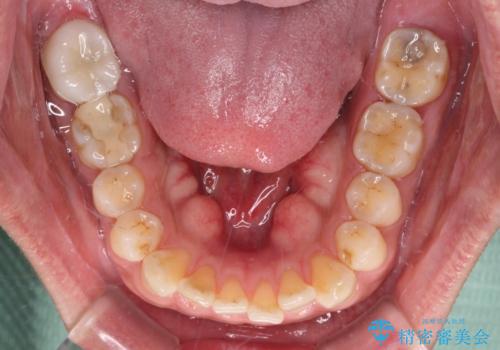

- 奥歯の間から出血するとのことで来院された患者様です。

口腔内は非常にきれいで、定期的に歯科医院でのクリーニングも行っているとのことでしたが、歯肉からの出血が一向に解決しない状態でした。

奥歯の歯間部の歯肉が炎症で赤黒くなっており、歯周ポケットを検査したところ、6-8mm(正常では3mm以下)であり、外科処置が適用となる状態でした。